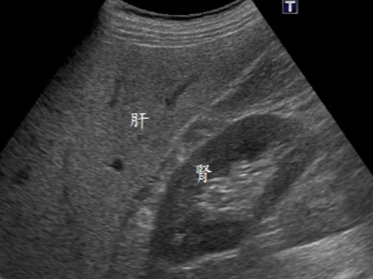

복부 초음파란?

복부 초음파는 인체의 복부 부위에 위치한 장기들을 고해상도 초음파로 들여다보는 비침습적 영상 검사입니다. 방사선 노출이 없고, 검사 시간이 짧으며, 비교적 저렴한 비용으로 복부 초음파로 알 수 있는 것이 많다는 장점 덕분에 다양한 복부 질환의 선별과 진단에 널리 사용됩니다.

복부 초음파로 알 수 있는 것

특히, 복통·복부 팽만·소화불량·황달 등의 증상 원인을 확인하거나 건강검진 목적으로 시행되기도 하며, 만성 질환자의 정기적인 추적검사 도구로도 쓰입니다.

주요 복부 초음파로 알 수 있는 것 (질병)

복부 초음파는 아래와 같은 장기와 관련된 질환 진단에 사용됩니다.

간(간장)

• 지방간, 간염(급성·만성), 간경변

• 간암, 간낭종, 간농양

• 간혈관종, 간의 종대 또는 위축

신장(콩팥)

• 신장결석, 수신증

• 신장종양(신세포암 등), 낭종

• 신우신염, 요로 폐쇄

• 다낭신증, 신장 위축

이처럼 복부 초음파는 단순히 '보는 검사'가 아니라, 질병을 빠르게 감별하거나 중대한 병변 여부를 스크리닝하는 데 필수적인 검사입니다.